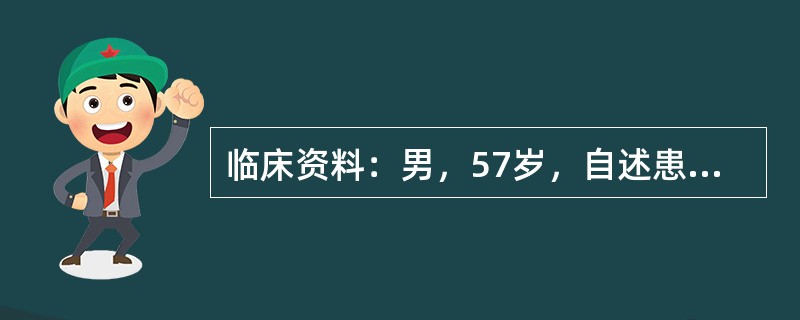

临床资料:男,57岁,自述患乙肝、肝硬化十余年。临床化验检查:CEA、AFP均升高。超声综合描述:彩图125(1):肝表面不平,实质回声粗糙不均,肝右叶可见3.1cm×3.2cm圆形低回声区,边界清晰,内回声欠均,CDFI:内见较丰富血流信号,为动脉波形,门静脉1.4cm,为入肝血流,血流通畅。彩图125(2):射频消融治疗后3天,肝右叶由低回声区一回声增强,周边缩瘪样改变,CDFI:内未见血流信号,周边可见散在点状血流信号。

A.彩图125(1)原发性肝癌;彩图125(2)射频消融后肿瘤血管灭活

B.彩图125(1)原发性肝癌;彩图125(2)射频消融后肿瘤周边血管灭活不彻底

C.彩图125(1)原发性肝癌;彩图125(2)射频消融后肿瘤内血管灭活不彻底

D.彩图125(1)原发性肝癌;彩图125(2)射频消融后肿瘤血管未灭活

[单选题]临床资料:男,57岁,自述患乙肝、肝硬化十余年。临床化验检查:CEA、AFP均升高。超声综合描述:彩图125(1):肝表面不平,实质回声粗糙不均,肝右叶可见3.1cm×3.2cm圆形低回声区,边界清晰,内回声欠均,CDFI:内见较丰富血流信号,为动脉波形,门静脉1.4cm,为入肝血流,血流通畅。彩图125(2):射频消融治疗后3天,肝右叶由低回声区一回声增强,周边缩瘪样改变,CDFI:内未见血流信号,周边可见散在点状血流信号。超声提示()A . 彩图125(1)原发性肝癌;彩图125